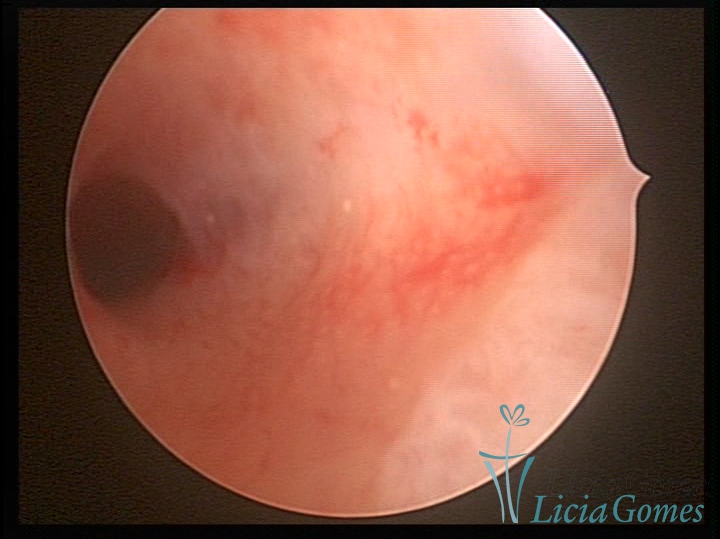

Unicornuate uterus

It presents a tubular cavity with an impaired intracavitary space, resembling the shape of a banana, whose the narrowest edge contains the tubal ostium. The endometrium is compatible with the menstrual cycle and the cervical canal is normal, in structure and trophism.